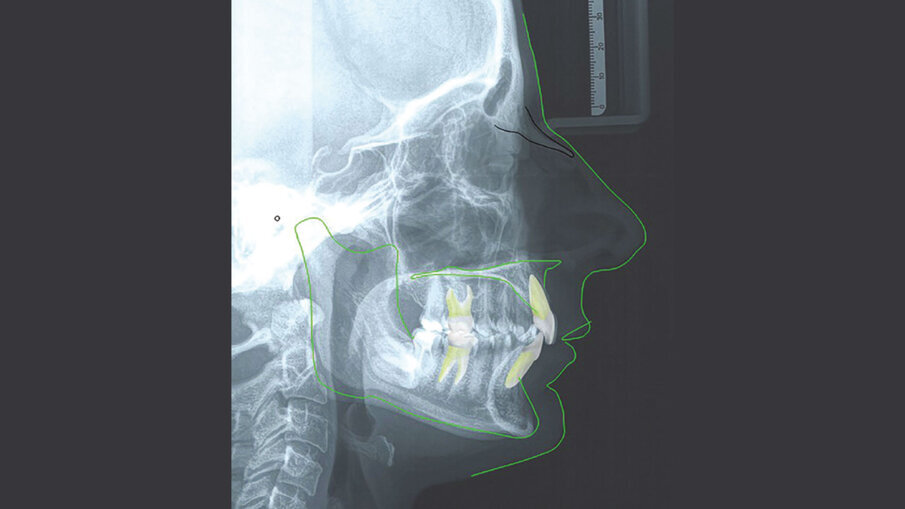

La paziente M. P. di anni 42 giunge alla nostra osservazione con la richiesta di un trattamento ortodontico di tipo estetico, al fine di migliorare l’allineamento dentale e l’esposizione del sorriso. All’analisi del volto si evidenzia un viso di forma quadrata, simmetrico ed un profilo dritto. All’esame funzionale non si rilevano disfunzioni dell’ATM. L’analisi cefalometrica (Figg. 3a-3c) evidenza una seconda classe scheletrica associata a ipodivergenza. Gli incisivi superiori presentano un’inclinazione rispetto al piano bispinale di 99,57° e la loro posizione rispetto alla linea A-Pg risulta nella norma. Gli incisivi inferiori (106,57°) sono protrusi rispetto al piano mandibolare e la loro posizione rispetto alla linea A-Pg risulta nella norma.

Figg. 3a-3c_Acquisizione dei records radiografici. Tracciato cefalometrico iniziale.

Figg. 3a-3c_Acquisizione dei records radiografici. Tracciato cefalometrico iniziale.

Figg. 3a-3c_Acquisizione dei records radiografici. Tracciato cefalometrico iniziale.

Figg. 9a-9c_Esami radiografici dopo il trattamento, con sovrapposizione sul piano SN. Questo ci mostra come, non potendo proclinare ulteriormente gli incisivi inferiori oltre la sinfisi per sfruttare l’intrusione relativa, l’apertura del morso è stata ottenuta sfruttando al massimo solo movimenti di intrusione assoluta, seppur minimi, e movimenti di intrusione relativa superiore ed estrusione posteriore parziale, considerando la difficoltà di quest’ultima, a causa della tipologia brachifacciale della paziente.

Figg. 9a-9c_Esami radiografici dopo il trattamento, con sovrapposizione sul piano SN. Questo ci mostra come, non potendo proclinare ulteriormente gli incisivi inferiori oltre la sinfisi per sfruttare l’intrusione relativa, l’apertura del morso è stata ottenuta sfruttando al massimo solo movimenti di intrusione assoluta, seppur minimi, e movimenti di intrusione relativa superiore ed estrusione posteriore parziale, considerando la difficoltà di quest’ultima, a causa della tipologia brachifacciale della paziente.

Figg. 9a-9c_Esami radiografici dopo il trattamento, con sovrapposizione sul piano SN. Questo ci mostra come, non potendo proclinare ulteriormente gli incisivi inferiori oltre la sinfisi per sfruttare l’intrusione relativa, l’apertura del morso è stata ottenuta sfruttando al massimo solo movimenti di intrusione assoluta, seppur minimi, e movimenti di intrusione relativa superiore ed estrusione posteriore parziale, considerando la difficoltà di quest’ultima, a causa della tipologia brachifacciale della paziente.

Figg. 9a-9c_Esami radiografici dopo il trattamento, con sovrapposizione sul piano SN. Questo ci mostra come, non potendo proclinare ulteriormente gli incisivi inferiori oltre la sinfisi per sfruttare l’intrusione relativa, l’apertura del morso è stata ottenuta sfruttando al massimo solo movimenti di intrusione assoluta, seppur minimi, e movimenti di intrusione relativa superiore ed estrusione posteriore parziale, considerando la difficoltà di quest’ultima, a causa della tipologia brachifacciale della paziente.